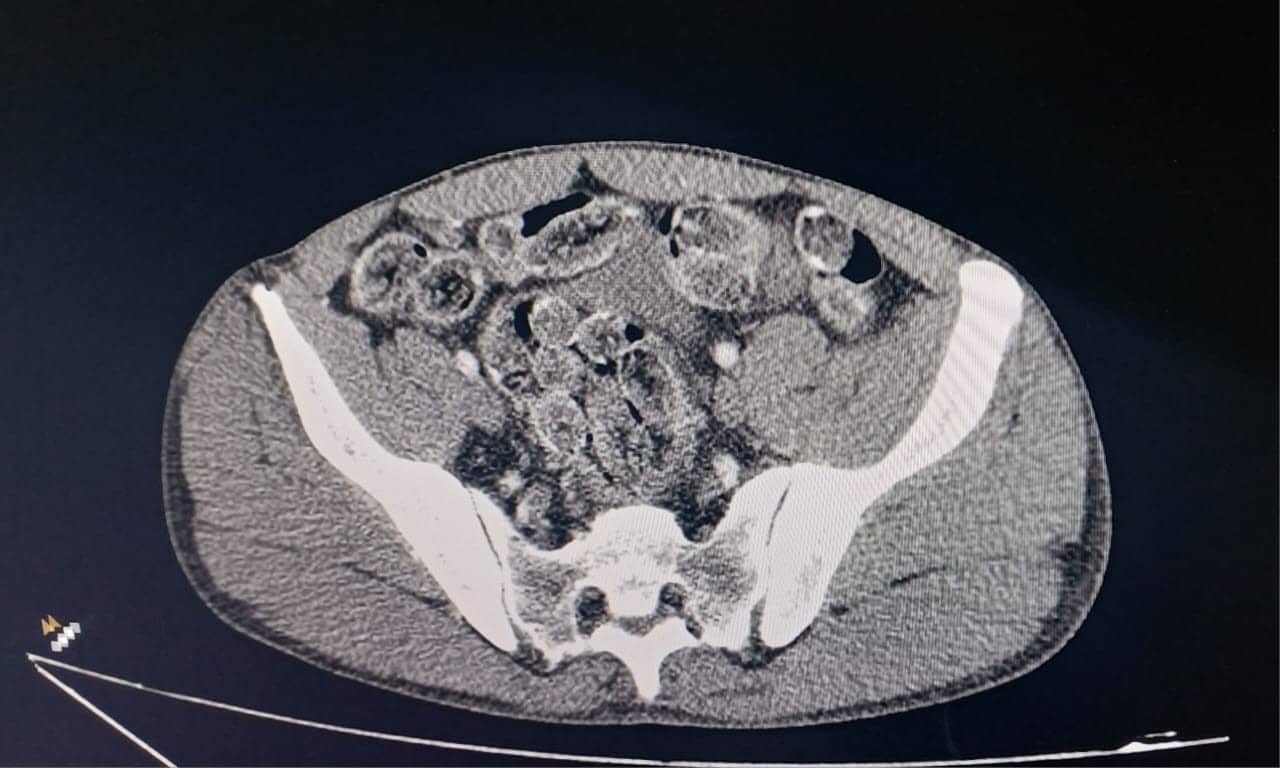

Dois dos detidos adotaram um método extremamente arriscado: a ingestão de cápsulas contendo droga. Após a abordagem, foram imediatamente encaminhados ao Conjunto Hospitalar de Sorocaba (CHS), onde exames confirmaram a presença de substâncias no estômago.

Os indivíduos passaram por procedimentos médicos para expelir as cápsulas, permanecendo sob observação hospitalar. A estratégia de “mulas” de drogas evidencia os riscos extremos assumidos por pessoas em situação de vulnerabilidade econômica.